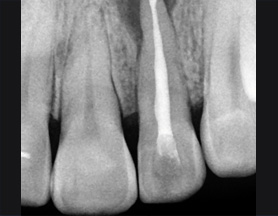

치근단 부위 회복

염증을 제거하는 신경치료 후 치근단 부위가 빠르게 회복되어 깔끔하게 신경치료를 완료하고 크라운 보철물을 씌웠습니다.

치근단 염증

신경관 소독

신경관 약재삽입

약재주입 후 반응